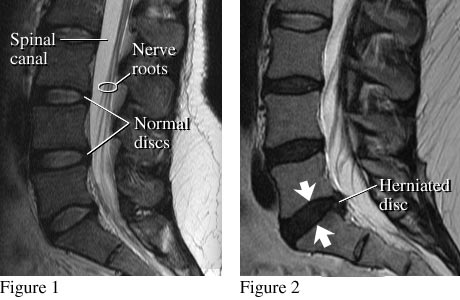

Chụp cộng hưởng từ cột sống thắt lưng (Lumbar Spine MRI) là một kỹ thuật chẩn đoán hình ảnh hiện đại sử dụng từ trường mạnh và sóng radio để tạo ra hình ảnh chi tiết của xương sống, đĩa đệm, tủy sống và các mô mềm vùng thắt lưng. Không giống như chụp X-quang hay CT, MRI không sử dụng tia bức xạ ion hóa, nên an toàn hơn, đặc biệt với phụ nữ mang thai và trẻ em.

MRI có thể dựng hình ảnh ở nhiều mặt phẳng khác nhau và phát hiện sớm những tổn thương nhỏ nhất. Kết quả chụp sẽ giúp bác sĩ xác định các vấn đề xảy ra ở cột sống, thắt lưng, đưa ra những chẩn đoán chính xác nhất.

| Thoát vị đĩa đệm | Xác định vị trí, mức độ chèn ép rễ thần kinh | |

| Hẹp ống sống | Đánh giá hẹp ống sống trung tâm hay lỗ liên hợp | |